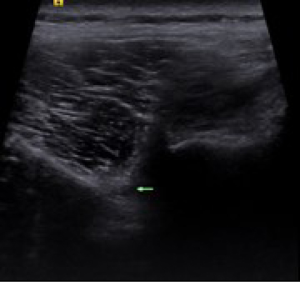

The observation group implemented percutaneous spinal nerve posterior medial branch lesion treatment to help patients assume the prone position and create bending of the lumbar. After routine disinfection, the surgical target area was determined using ultrasound guidance. The location of the posterior branches of the L3 and L4 was the cross-point of the upper articular processes of L4 and L5 and the corresponding transverse processes; the posterior branch of the L5 was the focal point of the superior articular process of S1 and the sacral wing (Figure 1). Next, 0.5% lidocaine (Chenxin Pharmaceutical Co., Ltd.; National Pharmaceutical Standard, H20043560) was used for local anesthesia, with the needle tip perpendicular to the nerve to ensure no blood, cerebrospinal fluid, or air were drawn back; furthermore, a radio frequency electrode was connected and set to a frequency of 50 Hz with the voltage between 0.3 and 0.5 V to give accurate positioning and test sensory function. High-frequency stimulation in the painful area was conducted to induce numbness and bloating, and subsequent exercise tests were performed. The set frequency was 2 Hz while the voltage was above 1 V; low frequency stimulation was conducted to induce contraction of the lower extremity muscles without causing motor nerve stimulation. If the sensory test was successful and the exercise test did not induce lower extremity exercise, radiofrequency thermocoagulation damage could proceed. The parameters were set to 72 °C (Celsius degree) for 60 s and 80 °C for 90 s. After the needle was withdrawn, the patient was instructed to lie down for 60 minutes. Patients were followed up for 6 months after operation.